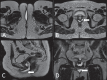

Magnetic resonance imaging is a method with high contrast resolution widely used in the assessment of pelvic gynecological diseases. However, the potential of such method to diagnose vaginal lesions is still underestimated, probably due to the scarce literature approaching the theme, the poor familiarity of radiologists with vaginal diseases, some of them relatively rare, and to the many peculiarities involved in the assessment of the vagina. Thus, the authors illustrate the role of magnetic resonance imaging in the evaluation of vaginal diseases and the main relevant findings to be considered in the clinical decision making process.